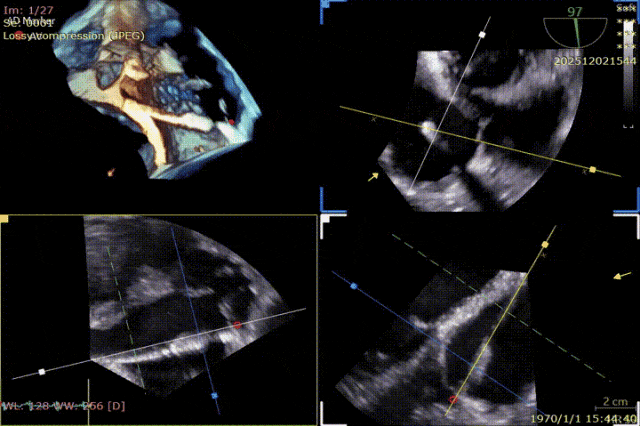

During the procedure, close collaboration was maintained with Dr. Yang Yan (anesthesiologist, Department of Anesthesiology) and Dr. Niu Ming (echocardiography specialist, team of Director Zhai Hong, Department of Cardiac Ultrasound). Guided by transesophageal echocardiography and assisted by DSA imaging, the tricuspid annular structure and regurgitation jet direction were precisely assessed. Ultimately, two 12T K-Clip® devices were successfully implanted. Immediate postoperative echocardiographic evaluation showed a significant reduction in tricuspid regurgitation from 4+ preoperatively to 1+, with a marked decrease in annular area. The surgical outcome was satisfactory.

First clip:

Advancement of the delivery system into the right atrium

Clip positioned toward the posterior annulus, slightly septal side.

Anchor screw advanced into the annulus.

Opening the clip and adjusting the orientation of the clip arms.

Lifting the annulus and closing the clip.

Evaluating the effect.